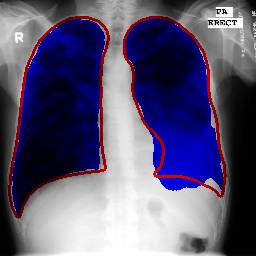

Repository features UNet inspired architecture used for segmenting lungs on chest X-Ray images.

Scores achieved on Montgomery and JSRT(With these masks. See preprocess_JSRT.py.) (Measured using 5-fold cross-validation):

| IoU | 0.971 | 0.956 |

| Dice | 0.985 | 0.972 |